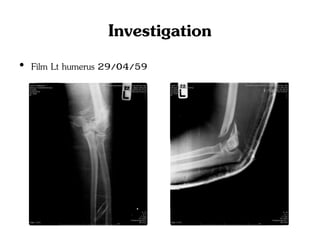

• Film Lt humerus 29/04/59

Investigation